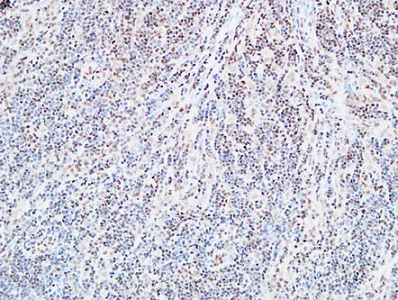

FEN-1 Rabbit Polyclonal Antibody

Cat: APRab10901